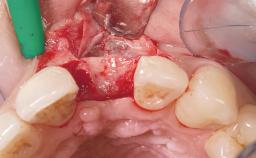

Immediate Flapless Placement of an Implant in a Maxillary Left Central Incisor Site

A 42-year-old female patient was referred to our clinic at the School of Dentistry of the University of São Paulo in November 2004, presenting a deficient restoration in the upper left central incisor. The clinical examination revealed no gingival retraction or any signs of gingival inflammation and, therefore, previous periodontal treatment was not considered. The patient presented a high lip line at full smile and a thin tissue biotype. This combination characterized a high-risk situation from an anatomic point of view, which required careful preoperative planning and cautious surgical execution.

Soft Tissue Grafting None

Placement Protocol Immediate implant placement

Socket Integrity Sufficient, with intact bone walls

Bone Volume Sufficient, with intact walls